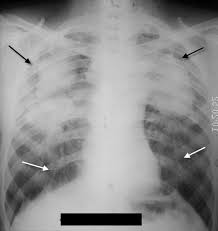

This finding on X-Ray shown by the black arrows indicates severely advanced silicosis

What is progressive massive fibrosis (PMF)?

*Formed by smaller nodules combining over time to make huge spots

The arrows on the X-Ray show this finding associated with silicosis

What are eggshell calcifications?

*Often at hilar lymph nodes